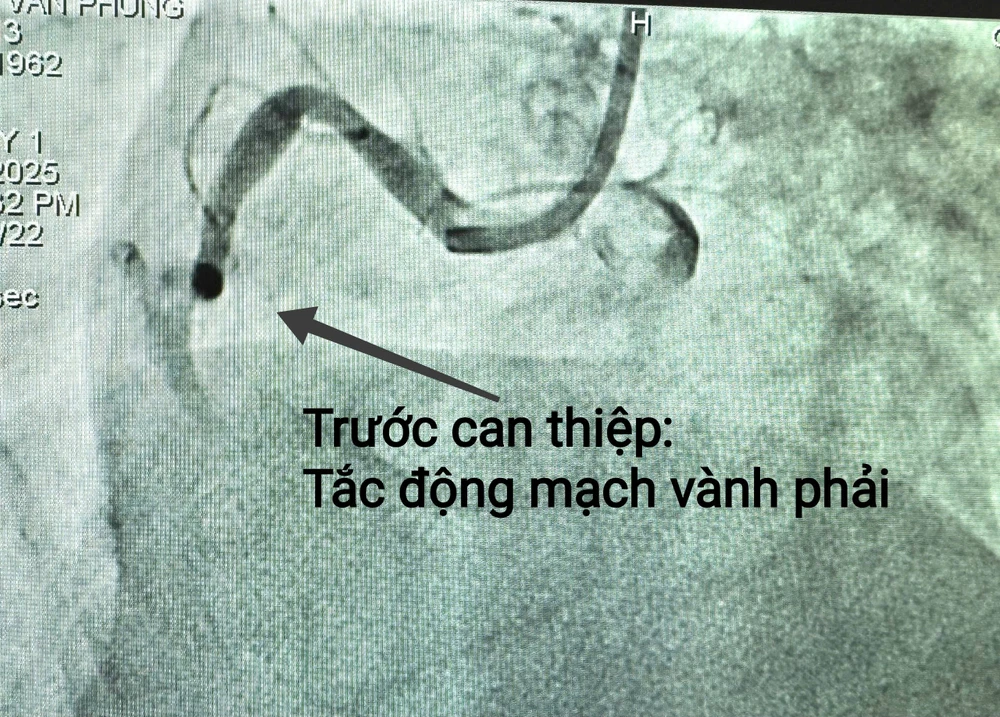

Hình ảnh tổn thương bệnh mạch vành, nhồi máu cơ tim của bệnh nhân P trước can thiệp. Ảnh: BVCC

Thay vì chờ đợi người nhà bệnh nhân đóng tiền, đội ngũ y, bác sĩ khoa Tim mạch can thiệp đã không để lãng phí cơ hội sống của bệnh nhân. Quy trình báo động đỏ nội viện được kích hoạt với phương châm “cứu người trước, viện phí tính sau”. Bệnh nhân nhanh chóng được đưa vào phòng can thiệp.

30 phút sau, ca can thiệp thành công, ê-kíp bác sĩ đã thành công mở lại dòng chảy của đoạn động mạch vành bị tắc. Chiếc stent phủ thuốc là "cứu tinh" giúp trái tim bệnh nhân P hồi sinh. Cả ê-kíp vỡ òa khi những dấu hiệu sinh tồn của bệnh nhân ổn định trở lại.